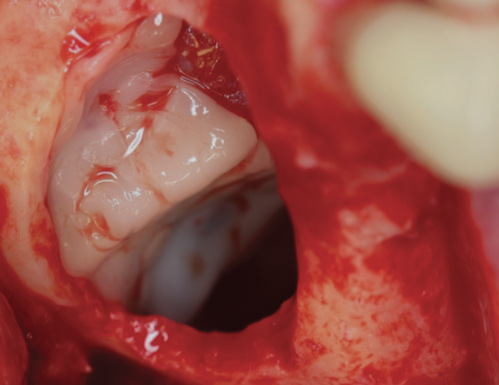

Fig 10. Small Schneiderian membrane perforation (arrow) during a standard lateral approach.

Figure 10

Fig 11. Schneiderian membrane perforation covered with a PRF membrane.

Figure 11

Another frequent use of PRF has been for the repair of Schneiderian membrane perforations (Figure 10 and Figure 11). While major advancements have been made with respect to surgical techniques, tools, and instruments to decrease the rate of membrane perforation, typical frequencies of tears generally have been reported in the 20% range.25,26 Traditionally, absorbable collagen membranes have been used most commonly; however, more recently attempts have been made to cover perforations with PRF. Due to the typically "sticky" consistency of PRF, this 100% natural fibrin scaffold may be used as a low-cost alternative to standard collagen membranes. Because of its natural properties, PRF, unlike a collagen barrier membrane, will not induce a foreign-body reaction.27

Figure 11 demonstrates a small Schneiderian membrane tear that was regenerated with PRF alone. However, it is recommended that tears larger than 5 mm be treated with a standard approach utilizing a collagen membrane. Nevertheless, the advantage of using PRF for perforations ≤5 mm in diameter is that the reparative process may be achieved with the aid of improved handling properties due to the sticky consistency of PRF without inducing a foreign-body reaction that may occur in response to collagen-derived biomaterial. As a rule, multiple layers of PRF may be utilized for larger tears, at virtually no additional cost. Because typical resorption periods are 10 to 14 days, it is advised to use PRF in a double layer to assure complete coverage (Figure 9). This also provides the added benefit of minimizing the risk of potential sinusitis that may be caused by low bone volume as a consequence of dramatic pneumatization after implant placement, owing to the cellular leukocyte content found in PRF.